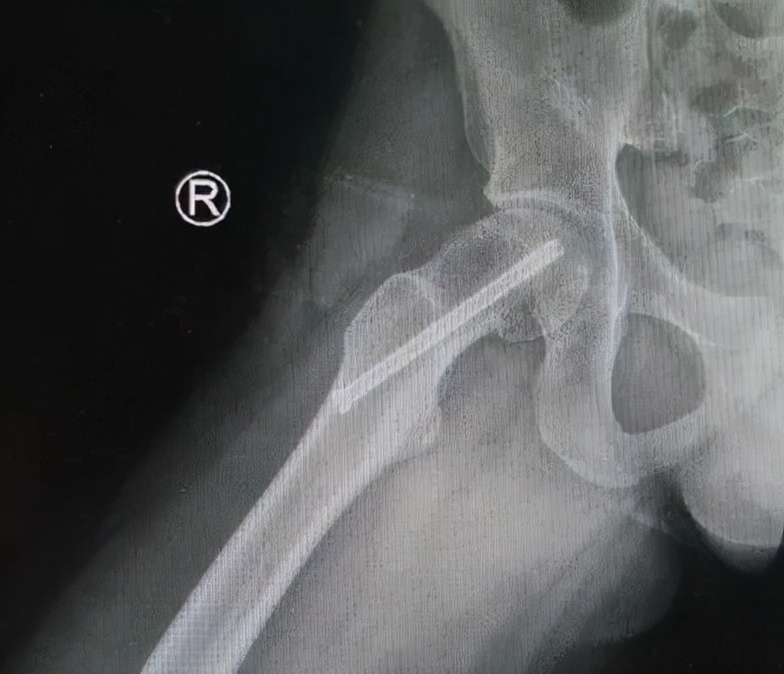

病例2 男,14岁,右侧重度SCFE,行闭合复位,经皮空心钉固定术

病例2 术后17个月复查,X线示位置良好,无股骨头缺血坏死发生